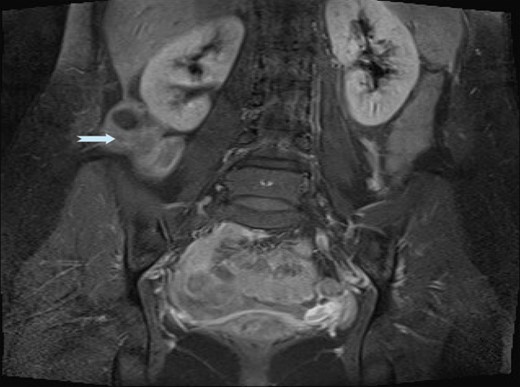

An ultrasound scan (USS) was performed and a 9 cm mass was demonstrated. A subsequent computer tomography (CT) scan confirmed the mass (Fig. 1) and raised the possibility that the mass may be a small bowel neuroendocrine tumour. The mass reported as separate from the appendix and caecum and no evidence of appendicitis. On the following day, the images were presented, the case was discussed at the colorectal multi-disciplinary team (MDT) meeting and a collective decision was made to perform a magnetic resonance imaging (MRI) scan which the patient underwent the following day. MRI was performed to specifically define the anatomy of the small bowel and its relation to the mass, as this was not clear on CT imaging. Ultimately, the MRI demonstrated a mass with vascular pedicle arising from the inferior aspect of the right hepatic lobe and the appearance raise the possibility of an exophytic liver lesion which has undergone torsion (Fig. 2). She was taken for a diagnostic laparoscopy the next day however given the size of the mass and the slim body habitus of the patient, a decision was made to convert to lower midline mini laparotomy.

MRI images demonstrating ALL with vascular pedicle attached to liver.